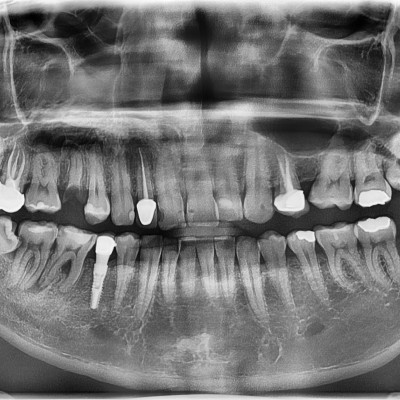

#18,28,48 사랑니 발치 #18,28,48 사랑니 발치 구강 외과 전문의가 당일 발치했습니다.